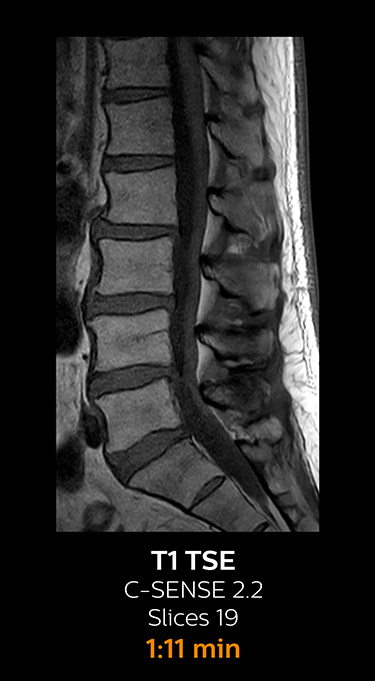

Fast MRI of lumbar spine

With Compressed SENSE, the scan time for the routine lumbar spine examination at KNC was reduced from 11:41 to 8:17 minutes,

which corresponds to 34% reduction.

MRI examination of lumbar spine with Compressed SENSE

MRI examination of the lumbar spine with Compressed SENSE

Ingenia 3.0T CX

Scan time 8:17 min. (was 11:41 min. without Compressed SENSE)